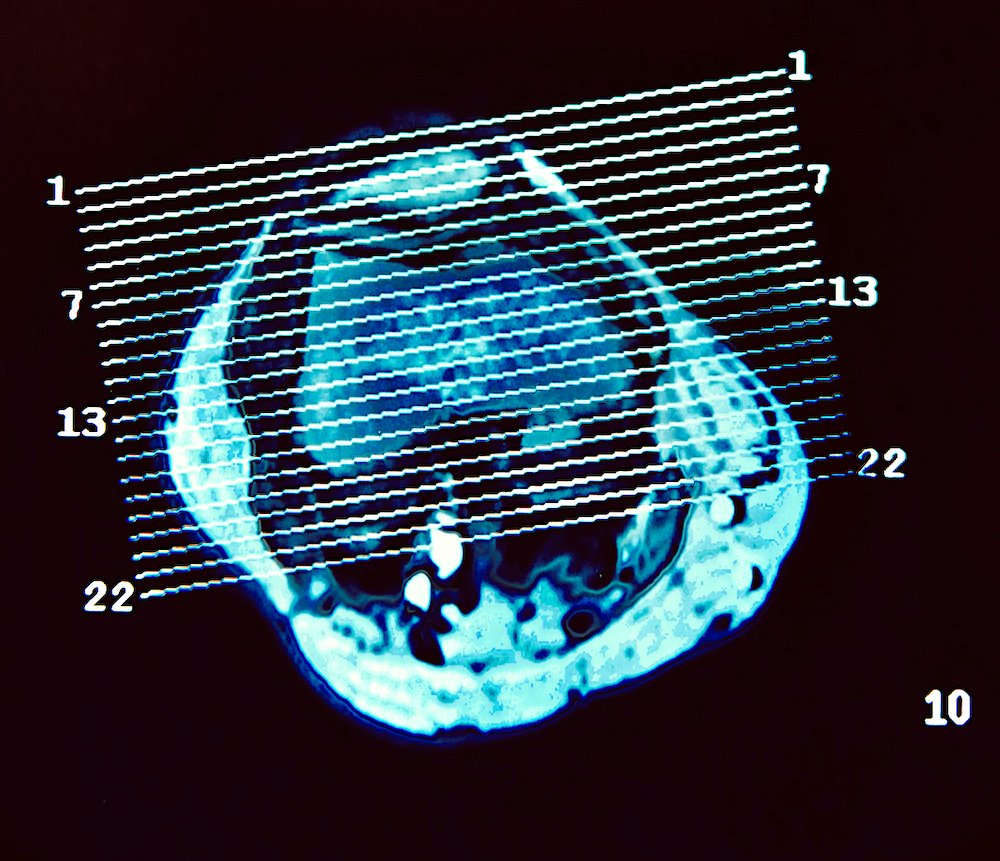

saturday night fever (girl meets boy diptych)

Selected for July/Aug 2022 exhibition in Art No.23’s Barcelona gallery.